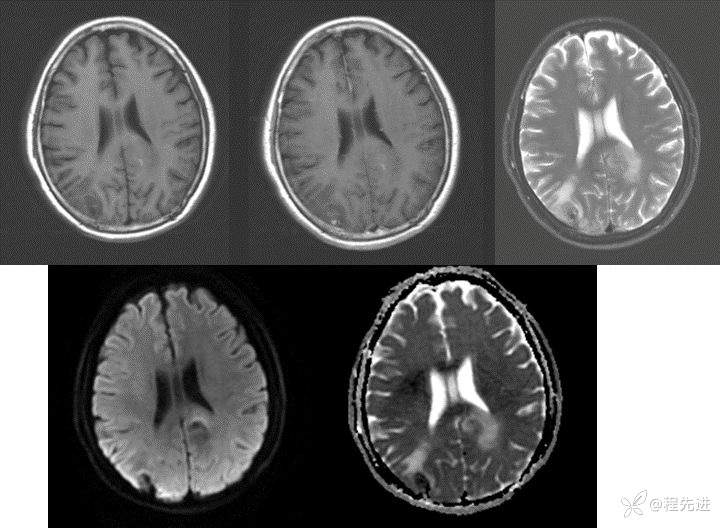

CT:

img

MRI: